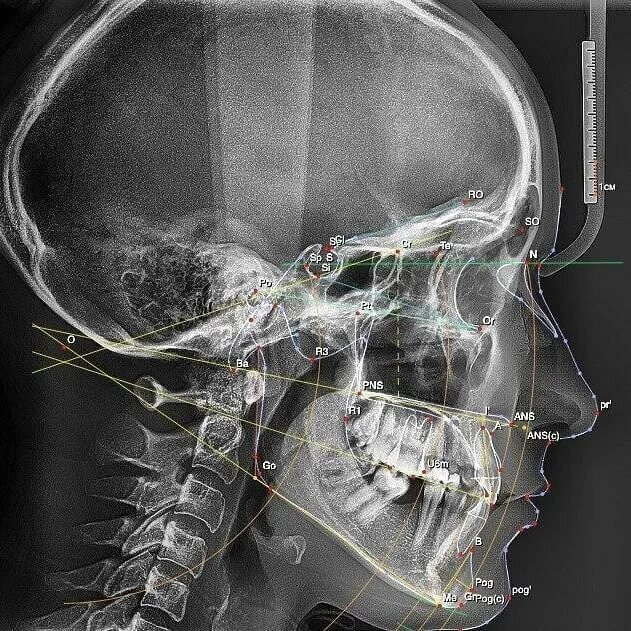

Трг проекции